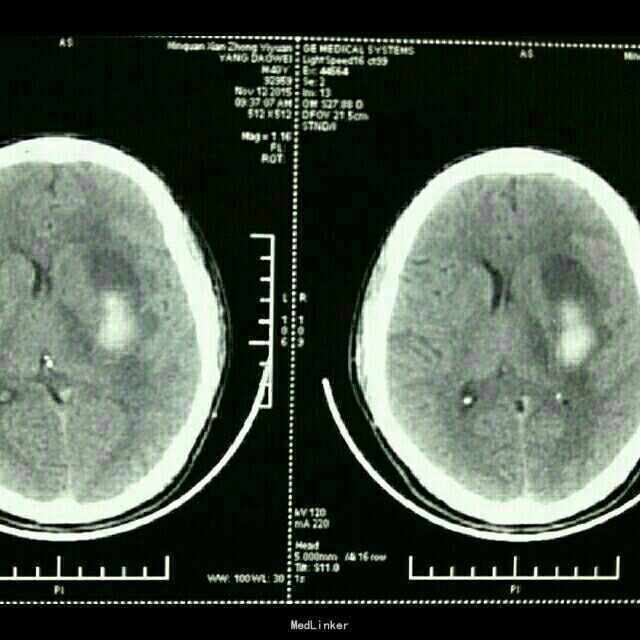

杨XX,男,40岁。 主诉:右侧上下肢无力伴失语15天。 病史:15天前在浙江务工时突然晕倒,随到浙江台州某医院就诊。神志清,精神差,查头颅CT示:“脑出血”,给予保守治疗。15天后家属要求转入原籍我院治疗。转入院时:神志清,精神可,血压:164/98mmHg,失语,右侧上下肢瘫痪,右侧上下肢肌力0级。 既往未检测血压。

诊断:高血压脑出血 治疗:微创钻孔血肿引流术。 术后应用尿激酶溶解血肿,引流顺利。 术后第四天拔除引流管。